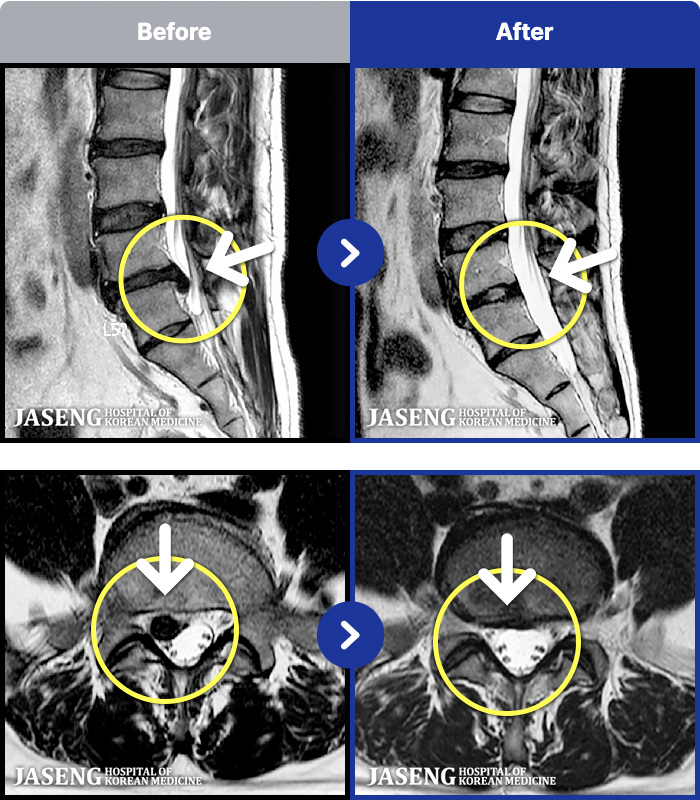

[뱸] 19.11.28~25.05.06

ȯںп Ǹ ǿ ԿǾ, ο ġ ۿ Ƿ ġḦ Ͻñ ٶϴ.